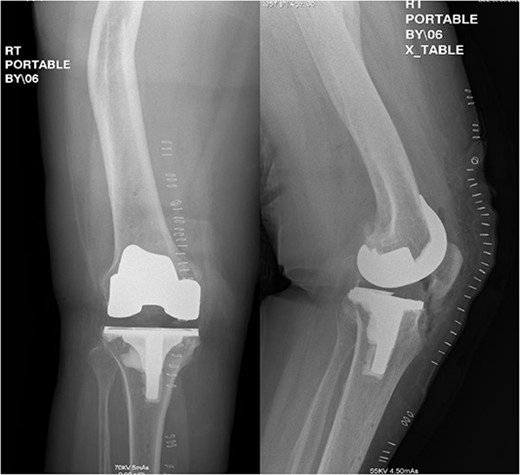

Postoperative anteroposterior and lateral radiograph views of the status of post RATKA.

Spinal regional anesthesia was performed, and 1 g of cephazolin was administered, followed by prepping and draping of the right lower limb in the usual sterile manner. After inflation of an above-knee tourniquet, a right knee midline incision followed by a medial para-patellar arthrotomy was performed. Knee joint exposure with proximal medial tibia release was carried out, followed by application of check points plus two pins in each of the tibia and the femur (navigation receptors). The hip center of rotation was registered, followed by medial and lateral malleolus registration. All large femoral and tibial osteophytes were resected, followed by mapping of articular cartilage in the femur and tibia. After mapping and balancing extension and flexion gaps (Fig. 3), the following sizes were determined: four for the femur and three for the tibia. The distal femur cut was carried out at 90° to the mechanical axis with robotic assistance, utilizing a burr and the remaining femoral cuts were completed with a distal femoral jig and electrical saw. The tibia cut could be achieved with an extramedullary guide, but a burr was utilized for added accuracy regarding the tibial slope and angle of the cut. A trial was performed after completion of the femoral and tibial cuts; it showed good stability in both flexion and extension, with maintained patellar tracking. Copious irrigation with 3 L of normal saline and local anesthesia for the posterior capsule of the knee was performed, followed by cementation and final components placement. Then, the tourniquet was deflated and hemostasis was confirmed, followed by closure in layers and sterile dressing application. Postoperative radiographs showed good positioning of the components (Fig. 4).